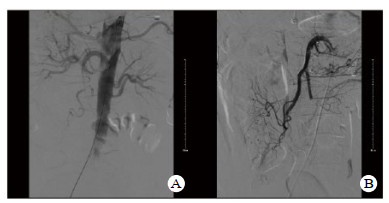

2 结果本组24例早期介入治疗患者,共19例患者肠梗阻症状逐渐缓解,临床治愈,治愈率79.2%。术后白细胞计数、D-二聚体指标与术前比较差异有统计学意义(P < 0.05),见表 1。其中18例MAET患者有经肠系膜上动脉造影后显示主干栓塞12例,空回肠动脉栓塞6例,经腔内介入治疗梗阻血管15例成功再通或侧枝开放(图 1),6例造影显示MVT患者经腔内介入治疗4例血栓基本溶解。另有3例MAET、2例MVT患者肠梗阻症状持续加重予以48 h内行剖腹探查术,予以肠系膜上动脉切开取栓3例,肠系膜静脉切开取栓1例,小肠部分切除4例,全小肠切除1例,其中3例术后恢复良好,2例因感染性休克、循环衰竭,围手术期死亡。

| 图 1 患者术前术后肠系膜上动脉造影结果(A:介入治疗术前造影提示肠系膜上动脉闭塞;B:介入治疗术后造影提示肠系膜上动脉开通) |